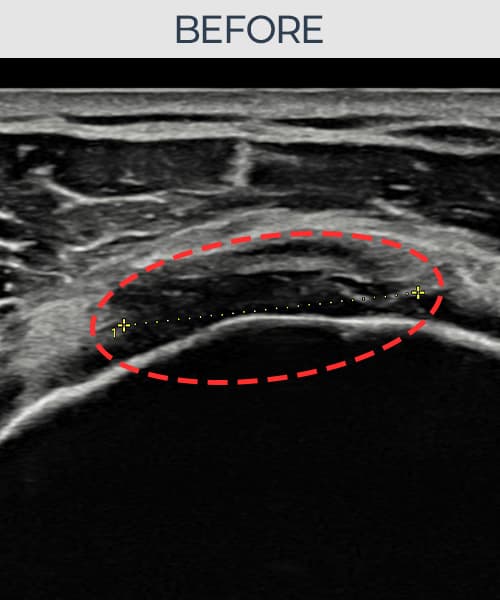

[촬영시기:23.07.18~23.09.14]

[어깨인대 축소봉합술] 좌측 어깨 광범위 파열로 수술을 권유받았으나 비수술 치료를 원해 내원하셨습니다.